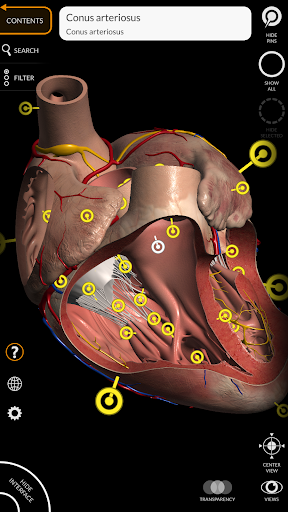

"Anatomy 3D Atlas" memungkinkan Anda mempelajari anatomi manusia dengan cara yang mudah dan interaktif.

Melalui antarmuka yang sederhana dan intuitif, Anda dapat mengamati setiap struktur anatomi dari sudut mana pun.

Model 3D anatomi sangat terperinci dan memiliki tekstur hingga resolusi 4k.

• Sistem kardiovaskular • Sistem

saraf • Sistem pernapasan • Sistem pencernaan • Sistem urogenital (pria dan wanita) • Sistem endokrin • Sistem limfatik • Sistem mata dan telinga FITUR • Antarmuka yang sederhana dan intuitif • Putar dan perbesar setiap model dalam ruang 3D • Opsi untuk menyembunyikan atau mengisolasi satu atau beberapa model yang dipilih • Filter untuk menyembunyikan atau menampilkan setiap sistem • Fungsi pencarian untuk menemukan setiap bagian anatomi dengan mudah • Fungsi penanda untuk menyimpan tampilan khusus • Rotasi cerdas yang menggerakkan pusat rotasi secara otomatis • Fungsi transparansi • Visualisasi otot melalui tingkat lapisan dari yang superfisial hingga yang terdalam • Dengan memilih model atau pin, istilah anatomi terkait akan muncul • Deskripsi otot: asal, • Tampilkan/ Sembunyikan antarmuka UI (sangat berguna dengan layar kecil) MULTIBAHASA • Istilah anatomi dan antarmuka pengguna tersedia dalam 11 bahasa: Latin, Inggris, Prancis, Jerman, Italia, Portugis, Turki, Rusia, Spanyol, Mandarin, Jepang, dan Korea • Istilah anatomi dapat ditampilkan dalam dua bahasa secara bersamaan PERSYARATAN SISTEM • Android 8.0 atau yang lebih baru, perangkat dengan RAM minimal 3GB Reversi

• Sistem kardiovaskular